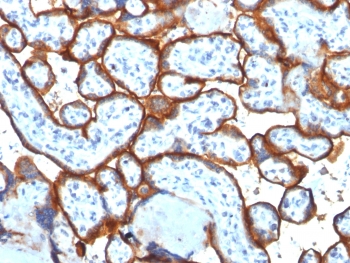

IHC testing of FFPE human placenta tissue with Transferrin Receptor / CD71 antibody (clone TFRC/1817). Required HIER: boil tissue sections in 10mM Tris with 1mM EDTA, pH 9, for 10-20 min followed by cooling at RT for 20 min.